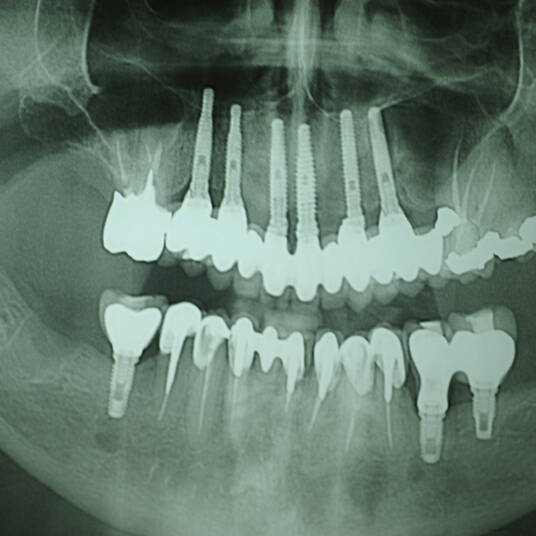

Na Clínica Pontes Odontologia, somos referência em implantes dentários em Fortaleza, oferecendo tratamentos de alta qualidade e tecnologia de ponta. Os implantes dentários são estruturas de titânio posicionadas cirurgicamente no osso maxilar ou mandibular para substituir as raízes dos dentes ausentes. Essa técnica permite a fixação de próteses personalizadas, restaurando a função mastigatória, a estética e a autoestima dos nossos pacientes.

Utilizamos a tecnologia CAD CAM, um sistema avançado que possibilita a confecção precisa das próteses dentárias diretamente sobre os implantes. Esse método inovador garante um ajuste perfeito, um resultado estético superior e proporciona muito mais conforto e durabilidade. Com o CAD CAM, nossos pacientes contam com um processo mais rápido e previsível para alcançar o sorriso desejado.